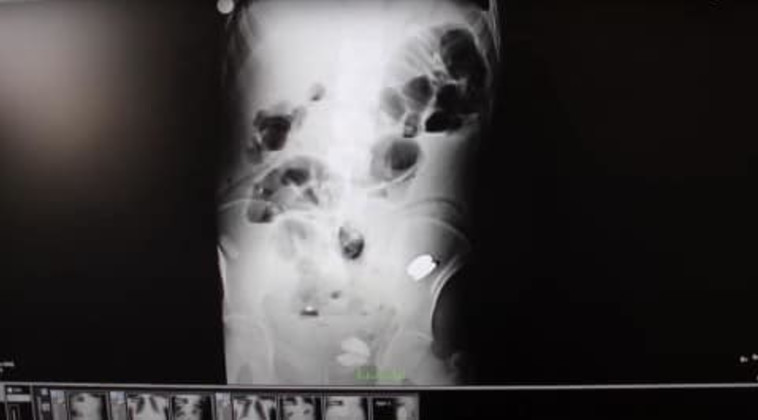

צילום הרנטגן מתוך הקיבה של המטופל

צילום הרנטגן מתוך הקיבה של המטופל | צילום: Ipakiolo hospital

בורהאן דמיר, אחיו של המטופל, הוביל אותו אל בית החולים בעיר איפקיולו אחרי שזה התלונן על כאבי בטן חמורים. כשהרופאים ביצעו בדיקת אנדוסקופיה, סריקות אולטרסאונד ורנטגן, התברר כי בתוך בטנו של המטופל התגלו מטבעות של לירה, סוללות, מגנטים, מסמרים, פיסות זכוכית, אבנים וברגים.

אחד המנתחים שלקח חלק בטיפול הרפואי, בשם ד"ר ביניצ'י, סיפר: "במהלך הניתוח ראינו ששני חתיכות זכוכית עברו דרך דופן הקיבה וראינו שיש גם במעי הגס חלקי מתכת ושתי אבנים. היינו בהלם כי זה לא מצב שרואים בדרך כלל אצל מבוגרים, אך ניקינו לו לבסוף את הבטן לגמרי".